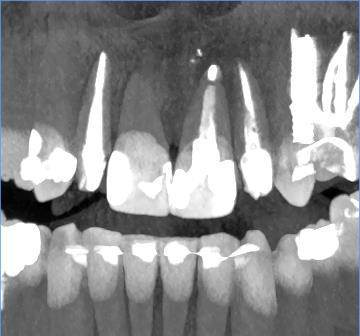

Есть зуб 11 (с СВШ) с восспалением около корня. До брекетов тоже было.

Перед протезированием предлагают перелечить каналы через корень с извлечением СВШ и последующим восстановлением (не понятно правда с СВШ или уже без него. Без СВШ зуб прям под корень может обломаться) под коронку.

До этого предлагали резекцию. Как в итоге лучше, через корень или резекцию?11-2.jpg.ba542aa82cfd6ddaad3fb9e234b99d99.jpg11.jpg.a34f40916e8e638d622001c50fff6e3a.jpg11-3.jpg.7a281f5893f8e6440937071fda10d523.jpg11-4.jpg.6a62c56e00cfdfa00cf35b7e276fd908.jpg